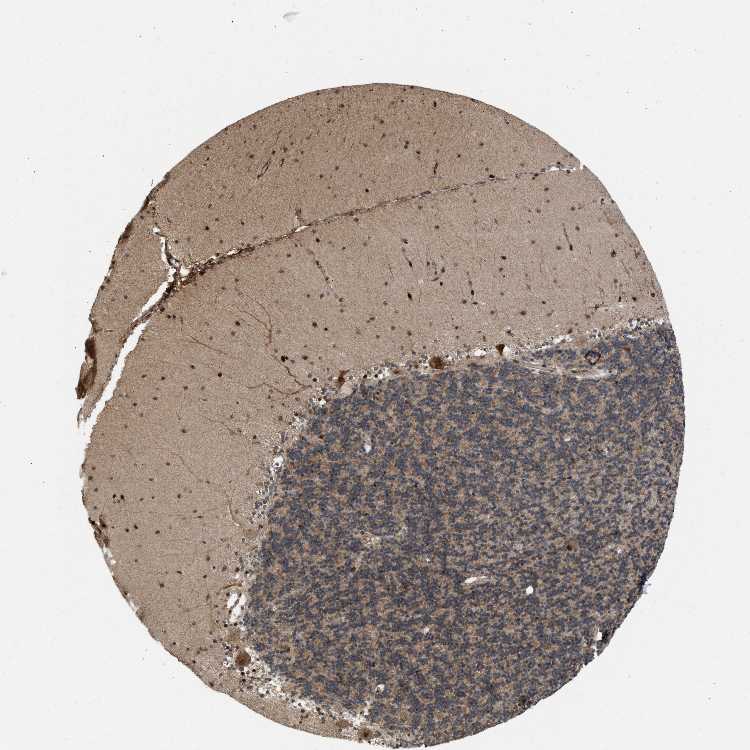

CEREBELLUM - Antibody stainingi

Antibody staining in the annotated cell types in the current human tissue is reported as not detected, low, medium, or high, based on conventional immunohistochemistry profiling in selected tissues. This score is based on the combination of the staining intensity and fraction of stained cells.

Each image is clickable and will lead to virtual microscopy that enables deeper exploration of all samples and also displays staining intensity scores, fraction scores and subcellular localization as well as patient and tissue information for each sample.

Antibody CAB019288

Purkinje cells High

Cells in granular layer Medium

Cells in molecular layer High